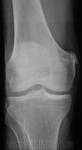

Женщина пожилого возраста пришла снимок коленей на предмет ДОА? ДОА есть, а перелом по типу П-Штиды? Я написал, что есть слева. А ваше мнение уважаемые коллеги?

Болезнь Пеллегрини - Штида проявляется обызвествлением мягких тканей в области внутреннего мыщелка бедра, что рентгенологически наблюдается в виде различных размеров теней. Клинически картина заболевания довольно неясная. После травмы появляются боли, чаще с внутренней стороны сустава. Сгибание ограничено. Пальпацией определяются болевые точки в области внутренного надмыщелка бедра выше уровня суставной щели. На фасной рентгенограмме коленного сустава обнаруживается костная тень в виде небольшого полулуния или скобки, расположенная на типичном месте у верхнего края внутреннего мыщелка бедра, параллельно его корковому слою, отделенная от него светлым промежутком. Этот костный участок является не отломком поверхностной пластинки коркового слоя, а обызвествлением или даже окостенением в сухожилии большой приводящей мышцы бедра. Киста мениска коленного сустава может располагаться как во внутреннем, так и наружном мениске. Последнее наблюдается гораздо чаще. Характерным является болезненность по соответствующей суставной щели, усиливающаяся при движении и нагрузке. Здесь же иногда видна припухлость, размер которой может варьировать.

В раннем периоде после травмы, когда клиническая картина идентична ушибу или дисторсии коленного сустава, а также при сочетании с внутренними повреждениями его диагностика затруднена. Через 3-4 недели после травмы на рентгенограммах коленного сустава определяют оссификат (рис.), имеющий вид скобки, серпа или неправильную форму, который отделен от надмыщелка бедренной кости полоской просветления. При отрицательных рентгенологических данных, но при наличии пальпируемого оссификата необходимо произвести рентгеновские снимки с внутренней или наружной ротацией конечности на 20° для устранения наслоения оссификата на контур мыщелка бедра. Информацию о степени зрелости оссификата может дать радионуклидное исследование. Дифференциальный диагноз проводят с отрывным переломом медиального надмыщелка бедренной кости, который выявляется на рентгенограмме сразу после травмы. Кроме того, краевой дефект надмыщелка по форме и размерам соответствует оторванному фрагменту кости. Похожую рентгенологическую картину можно наблюдать при перестроенном процессе в надмыщелке тракционного генеза, возникающем в результате многократных форсированных напряжений большой приводящей мышцы бедра, например у футболистов. Однако постепенное развитие этого заболевания, более молодой возраст, связь с занятиями спортом помогают уточнить диагноз.